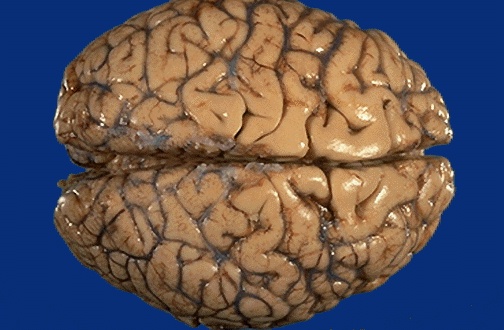

| Here is the vertex of a normal brain. Note the regular pattern of gyri and sulci. A sulcus is the depth between one gyrus and the next. The thin meninges cover the surface, but have been stripped away over part of the central fronto-parietal region at the right to reveal more clearly the sulci. The central fissure is where the extension of the dura between the hemispheres, called the falx cerebri, would be. |